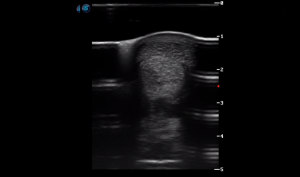

SIMON Ultrasound Database

This ultrasound database is a free resource for students and doctors!

Our collection includes videos of dogs, cats, horses, cows, humans, and many other species!